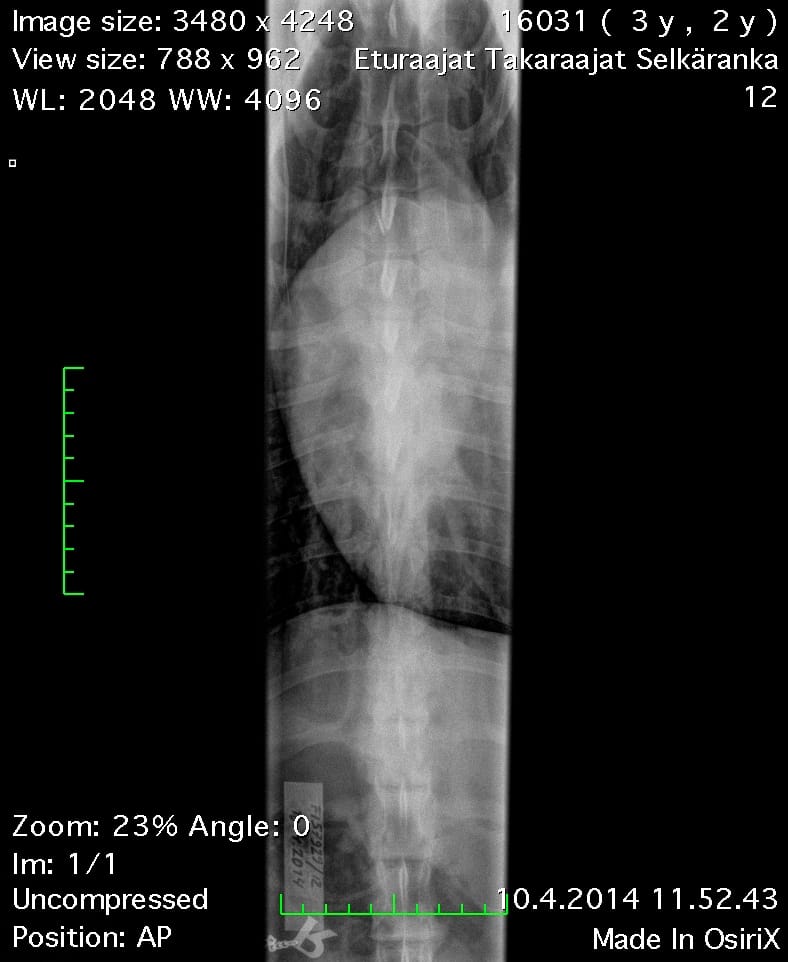

| Spine: | SP0, LTV4 (8 lumbosacral vertebrae) | |